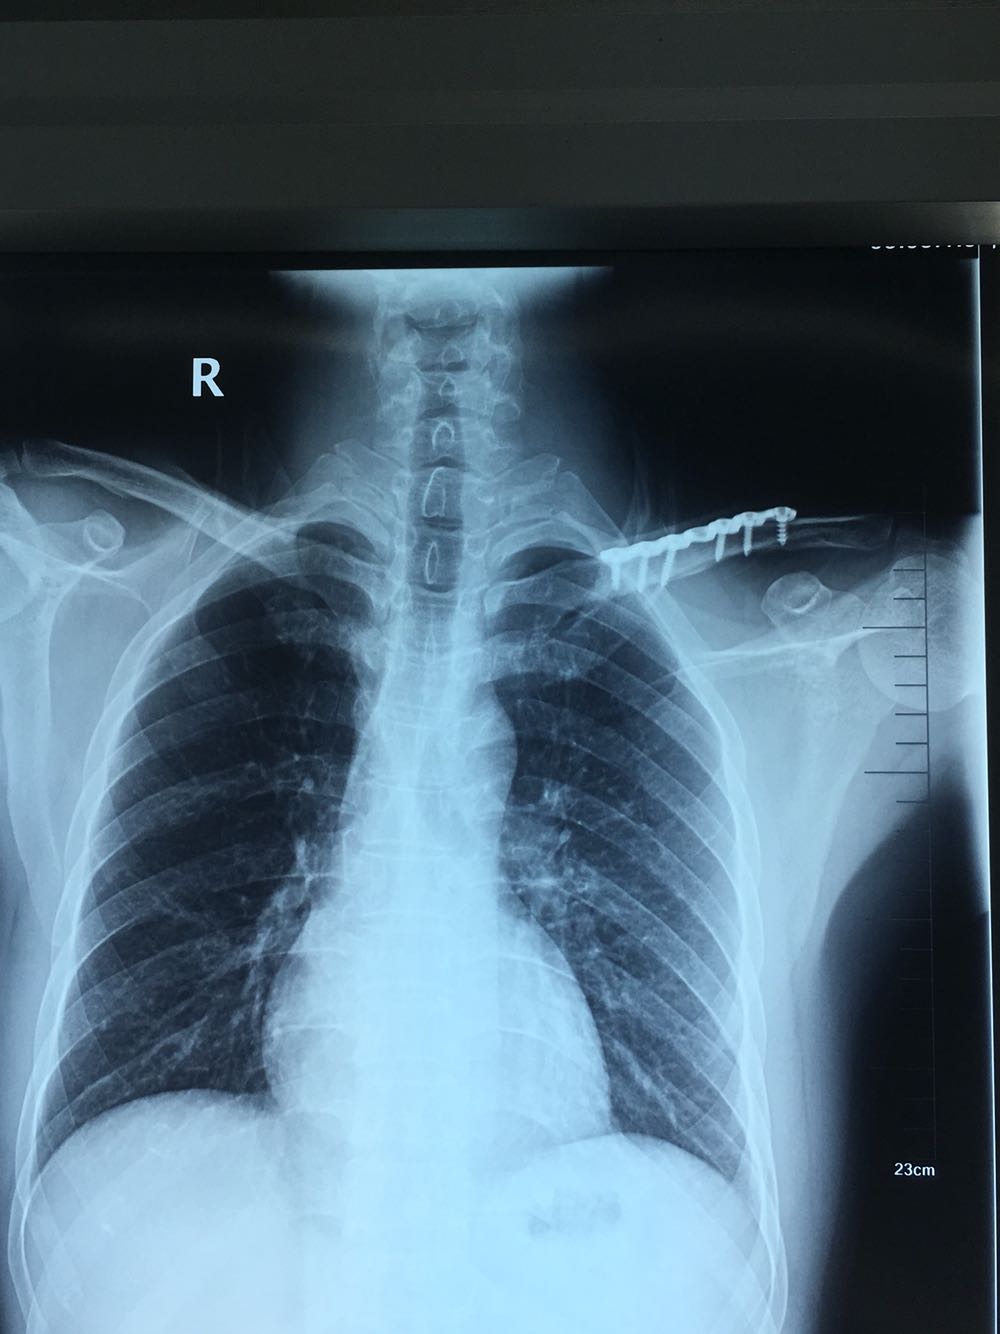

主诉:上颌骨骨折及锁骨骨折术后1年要求拆除内固定装置

治疗:全麻下双侧上颌骨骨折术后留置钛板取出及锁骨骨折术后钢板取出